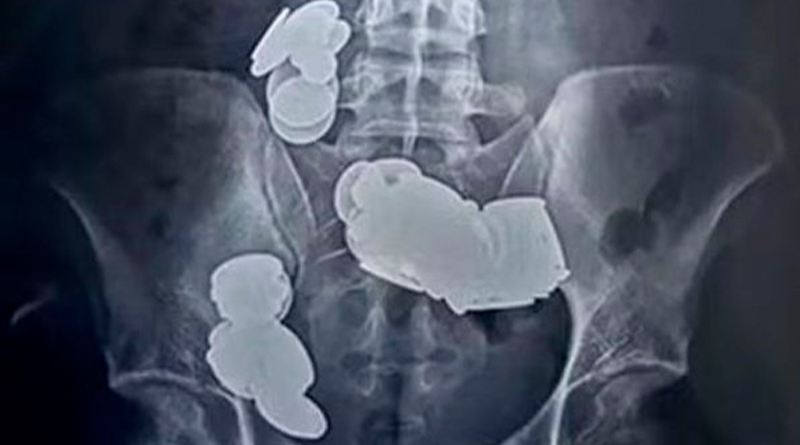

(Foto: reprodução/Sir Ganga Ram Hospital)- Uma equipe de médicos removeu 39 moedas e 37 ímãs do intestino de um jovem, o paciente acreditava que ao ingeri-los ajudaria na musculação. O caso foi registrado em Nova Délhi, na Índia e relatado recentemente.

Uma radiografia do abdômen do paciente revelou as moedas e ímãs. Os itens foram removidos em cirurgia.